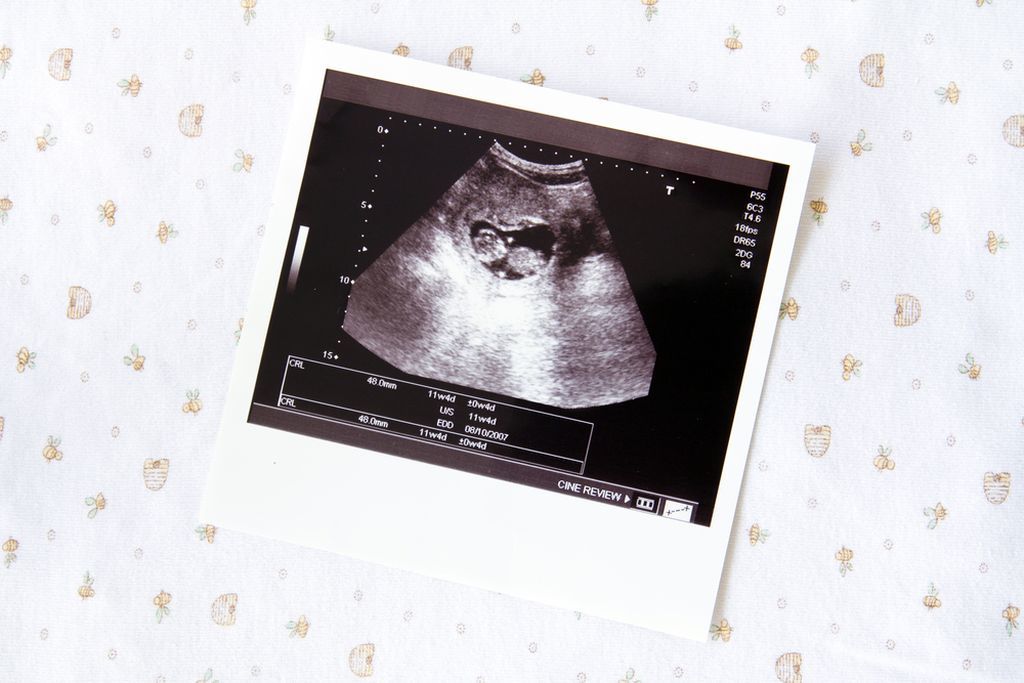

Η είδηση έρχεται ξαφνικά. Το τεστ εγκυμοσύνης βγήκε θετικό. Συμβαίνουν αυτά. Να, όμως, που θυμόμαστε εκείνη την ημέρα που πήραμε τα χάπια για τον πονοκέφαλο, φάγαμε εκείνο το παράξενο φαγητό με το ωμό κρέας, πήγαμε στον οδοντίατρο για εκείνο το σφράγισμα. Είχαμε ήδη συλλάβει το μωρό τότε; Οι αμφιβολίες μας κατακλύζουν και η χαρά γίνονται εφιάλτης. Υπάρχει πράγματι λόγος να φοβόμαστε κάποια ανεπανόρθωτη ζημιά; Όλα εξαρτώνται από τη στιγμή κατά την οποία συμβαίνει το περιστατικό, λένε οι ειδικοί. Εάν συμβεί σε πολύ πρώιμη φάση, όταν το έμβρυο δεν έχει φθάσει ακόμη στη μήτρα και δεν έχει δημιουργήσει ζωτικές σχέσεις με τον οργανισμό της μητέρας δεν υπάρχει λόγος ανησυχίας. Συνήθως η ίδια η φύση φροντίζει να κάνει τις επιλογές της. Εάν το ωάριο υποστεί σοβαρή βλάβη προκαλείται αποβολή, που συχνά εμείς την αντιλαμβανόμαστε ως καθυστέρηση στον κύκλο. Διαφορετικά η κύηση συνεχίζεται. Είναι ο κανόνας του «όλα ή τίποτα». Αλλά και πάλι, παρότι ο κίνδυνος δεν πρέπει να υποτιμάται, ιδίως στην περίοδο από την τρίτη έως την εντεκάτη εβδομάδα κατά την οποία διαμορφώνονται τα όργανα του εμβρύου, το μυαλό μας δεν πρέπει να πηγαίνει στο χειρότερο. Εάν υποψιάζεστε ότι κάνατε κάτι επικίνδυνο χωρίς να ξέρετε ότι είστε έγκυος, καλό είναι άμεσα να πάρετε τη συμβουλή του γυναικολόγου σας, ο οποίος με τη βοήθεια των υπερήχων θα εντοπίσει με ακρίβεια το χρόνο έναρξης της κύησης και με αυτόν τον τρόπο θα εκτιμηθεί η πιθανότητα ύπαρξης επιπτώσεων, γιατί δεν συνεπάγονται κίνδυνο όλες οι περιπτώσεις. Επίσης, υπάρχουν εξειδικευμένα κέντρα στα μεγάλα δημόσια νοσοκομεία, που καθορίζουν τον κίνδυνο βλαβών του εμβρύου, αν εκτεθεί η μητέρα σε κάποιο βλαπτικό παράγοντα. Πόσο επικίνδυνα είναι τα φάρμακα; Έχει αποδειχτεί ότι τα φάρμακα ευρείας χρήσης είναι τα λιγότερο επικίνδυνα. Για παράδειγμα, τα πιο κοινά φάρμακα για τη γρίπη, τον πονόδοντο ή τον πονοκέφαλο, όπως αυτά που έχουν βάση το ακετυλοσαλικιλικό οξύ, την παρακεταμόλη ή τα αντιφλεγμονώδη, δεν προκαλούν βλάβες στο έμβρυο κατά τις πρώτες εβδομάδες της κύησης. Ακόμη και ορισμένα αντιβιοτικά, όπως η αμοξυσιλίνη και οι πενικιλίνες, δεν έχουν παρενέργειες για το μικρό. Αυτό βέβαια δεν σημαίνει ότι μπορούμε να παίρνουμε ανεξέλεγκτα φάρμακα, κυρίως εάν θέλουμε να συλλάβουμε παιδί. Τα πιο επικίνδυνα είναι τα φάρμακα κατά της επιληψίας, τα αντικαταθλιπτικά, η βιταμίνη Α σε πολύ μεγάλες δόσεις, που χορηγείται για ορισμένες δερματικές παθήσεις. Κίνδυνος από ακτίνες Χ Οι ακτινογραφίες προκαλούν μεγάλο φόβο, αλλά με εξαίρεση την ακτινογραφία στην κοιλιά, σε οποιαδήποτε άλλη περιοχή του σώματος της μαμάς, ακόμη και στα δόντια, δεν προκαλούν βλάβη στο έμβρυο. Αντίθετα, οι ακτινογραφίες στην κοιλιά έχουν σοβαρές συνέπειες και μόνο πολύ ακριβείς εξετάσεις μπορούν να διαπιστώσουν εάν έχει προκληθεί βλάβη. Ακόμη και για την αξονική τομογραφία χρειάζεται προσοχή. Είναι μια εξέταση που συνήθως περιλαμβάνει πολλές ακτινογραφίες μερικές από τις οποίες μπορεί να αφορούν την περιοχή της κοιλιάς. Στον οδοντίατρο χωρίς φόβο Έχει αποδειχτεί ότι τα μείγματα που χρησιμοποιούνται για τα σφραγίσματα δεν προκαλούν βλάβη στο παιδί. Αυτό ισχύει ακόμη και για την αναισθησία, καθώς οι ουσίες που χρησιμοποιούνται είναι πολύ ελαφρές και δεν επηρεάζουν την κύηση. Σημαντική είναι η αποφυγή της αδρεναλίνης κατά την αναισθησία, γεγονός που γνωρίζουν βέβαια οι οδοντίατροι. Αντίθετα, μπορεί να αποδειχτεί επικίνδυνη η παραμέληση της στοματικής υγιεινής, τόσο λόγω της βλάβης στο σμάλτο των δοντιών όσο και λόγω των βακτηρίων των ούλων που εισέρχονται στο αίμα και δημιουργούν προδιάθεση για πρόωρο τοκετό. Ποιος κοινός ιός; Εκτός από την ερυθρά, οι άλλες κλασικές μολυσματικές ασθένειες, από την ιλαρά έως την ανεμοβλογιά (που είναι επικίνδυνη μόνο κατά το τελευταίο τρίμηνο της κύησης γιατί μπορεί να μεταδοθεί στο παιδί στη διάρκεια του τοκετού), δεν δημιουργούν σοβαρούς κινδύνους. Τα βακτήρια της γρίπης ή άλλων εποχιακών νόσων, της ωτίτιδας ή της αμυγδαλίτιδας, συνήθως δεν βλάπτουν το έμβρυο. Όλα βέβαια εξαρτώνται από τη φάση της κύησης. Άλλη περίπτωση που προκαλεί μεγάλο φόβο είναι η τοξοπλάσμωση, μια λοίμωξη που μπορεί να μεταδοθεί από ωμό κρέας, φρούτα και λαχανικά που δεν πλύθηκαν καλά. Εάν η μέλλουσα μαμά υποψιάζεται ότι βρέθηκε σε επικίνδυνη κατάσταση καλό είναι να κάνει αμέσως εξετάσεις για τις ανοσοσφαιρίνες (ΙgG, IgA, IgM). Αλλά, ακόμη κι αν βγουν θετικές, δεν υπάρχει λόγος πανικού. Σήμερα, μόνο στο 2,5 τοις χιλίοις η λοίμωξη μεταδίδεται στο παιδί και από αυτές τις περιπτώσεις μόνο στο ένα δέκατο αναπτύσσονται σοβαρές βλάβες. Συνήθως η τοξοπλάσμωση θεραπεύεται με αντιβιοτικό που επιτρέπει στις περισσότερες περιπτώσεις την καλύτερη έκβαση της εγκυμοσύνης. Η πιο σημαντική λοίμωξη από ιό, είναι αυτή από τον Κυτταρομεγαλοιό ή CMV. Είναι ένας ιός που όταν έρθει σε επαφή η μητέρα δεν δίνει ιδιαίτερα συμπτώματα, παρά μόνο την αίσθηση ενός ελαφρού κρυολογήματος, με καταρροή. Οι βλάβες όμως που μπορεί να προκαλέσει στο έμβρυο κατά το πρώτο τρίμηνο, είναι μεγάλες. Κυρίως προσβάλει την καρδιά και τον εγκέφαλο, με αποτέλεσμα να έχουμε μωρά μη συμβατά με τη ζωή και να χρειασθεί να κάνουμε διακοπή εγκυμοσύνης. Για το λόγο αυτό, είναι απαραίτητη η εξέταση για λοίμωξη από το CMV και δίδεται σε κάθε προγεννητικό έλεγχο. Δυστυχώς, η μητέρα δεν μπορεί να κάνει κάτι για να αποφύγει μια δυνητική λοίμωξη. Ερυθρά, η τρομερή Είναι η πιο επικίνδυνη περίπτωση. Εάν εκδηλωθεί κατά τους δύο πρώτους μήνες της εγκυμοσύνης μπορεί να έχει πολύ σοβαρές συνέπειες στο παιδί. Γι’ αυτό πρέπει να καταφύγετε αμέσως σε κάποιο εξειδικευμένο κέντρο ώστε να ακολουθήσετε τις καταλληλότερες προφυλάξεις. Εάν αντίθετα κάνατε επίτηδες προληπτικό εμβόλιο κατά της ερυθράς και μείνατε έγκυος πριν περάσει το διάστημα ασφαλείας των τριών μηνών, μην πανικοβληθείτε. Δεν έχει αποδειχτεί ότι το εμβόλιο μπορεί να προκαλέσει ζημιά στο έμβρυο. Τα εμβόλια Το αντιγριπικό δεν είναι επικίνδυνο γιατί στα εμβόλια χρησιμοποιούνται εξασθενημένοι ιοί, ωστόσο συνιστάται στις εγκύους μόνο σε ιδιαίτερες περιπτώσεις. Επικίνδυνα κατά τις πρώτες φάσεις της σύλληψης δεν θεωρούνται ούτε τα εμβόλια κατά της ηπατίτιδας Α και Β και ο αντιτετανικός ορός. Εάν λοιπόν έχετε κάνει κάποιο από αυτά τα εμβόλια, το μωρό δεν διατρέχει κανένα κίνδυνο. Με την συνεργασία της κας Μαρίας Παπαδοπούλου (μαιευτήρας – γυναικολόγος)